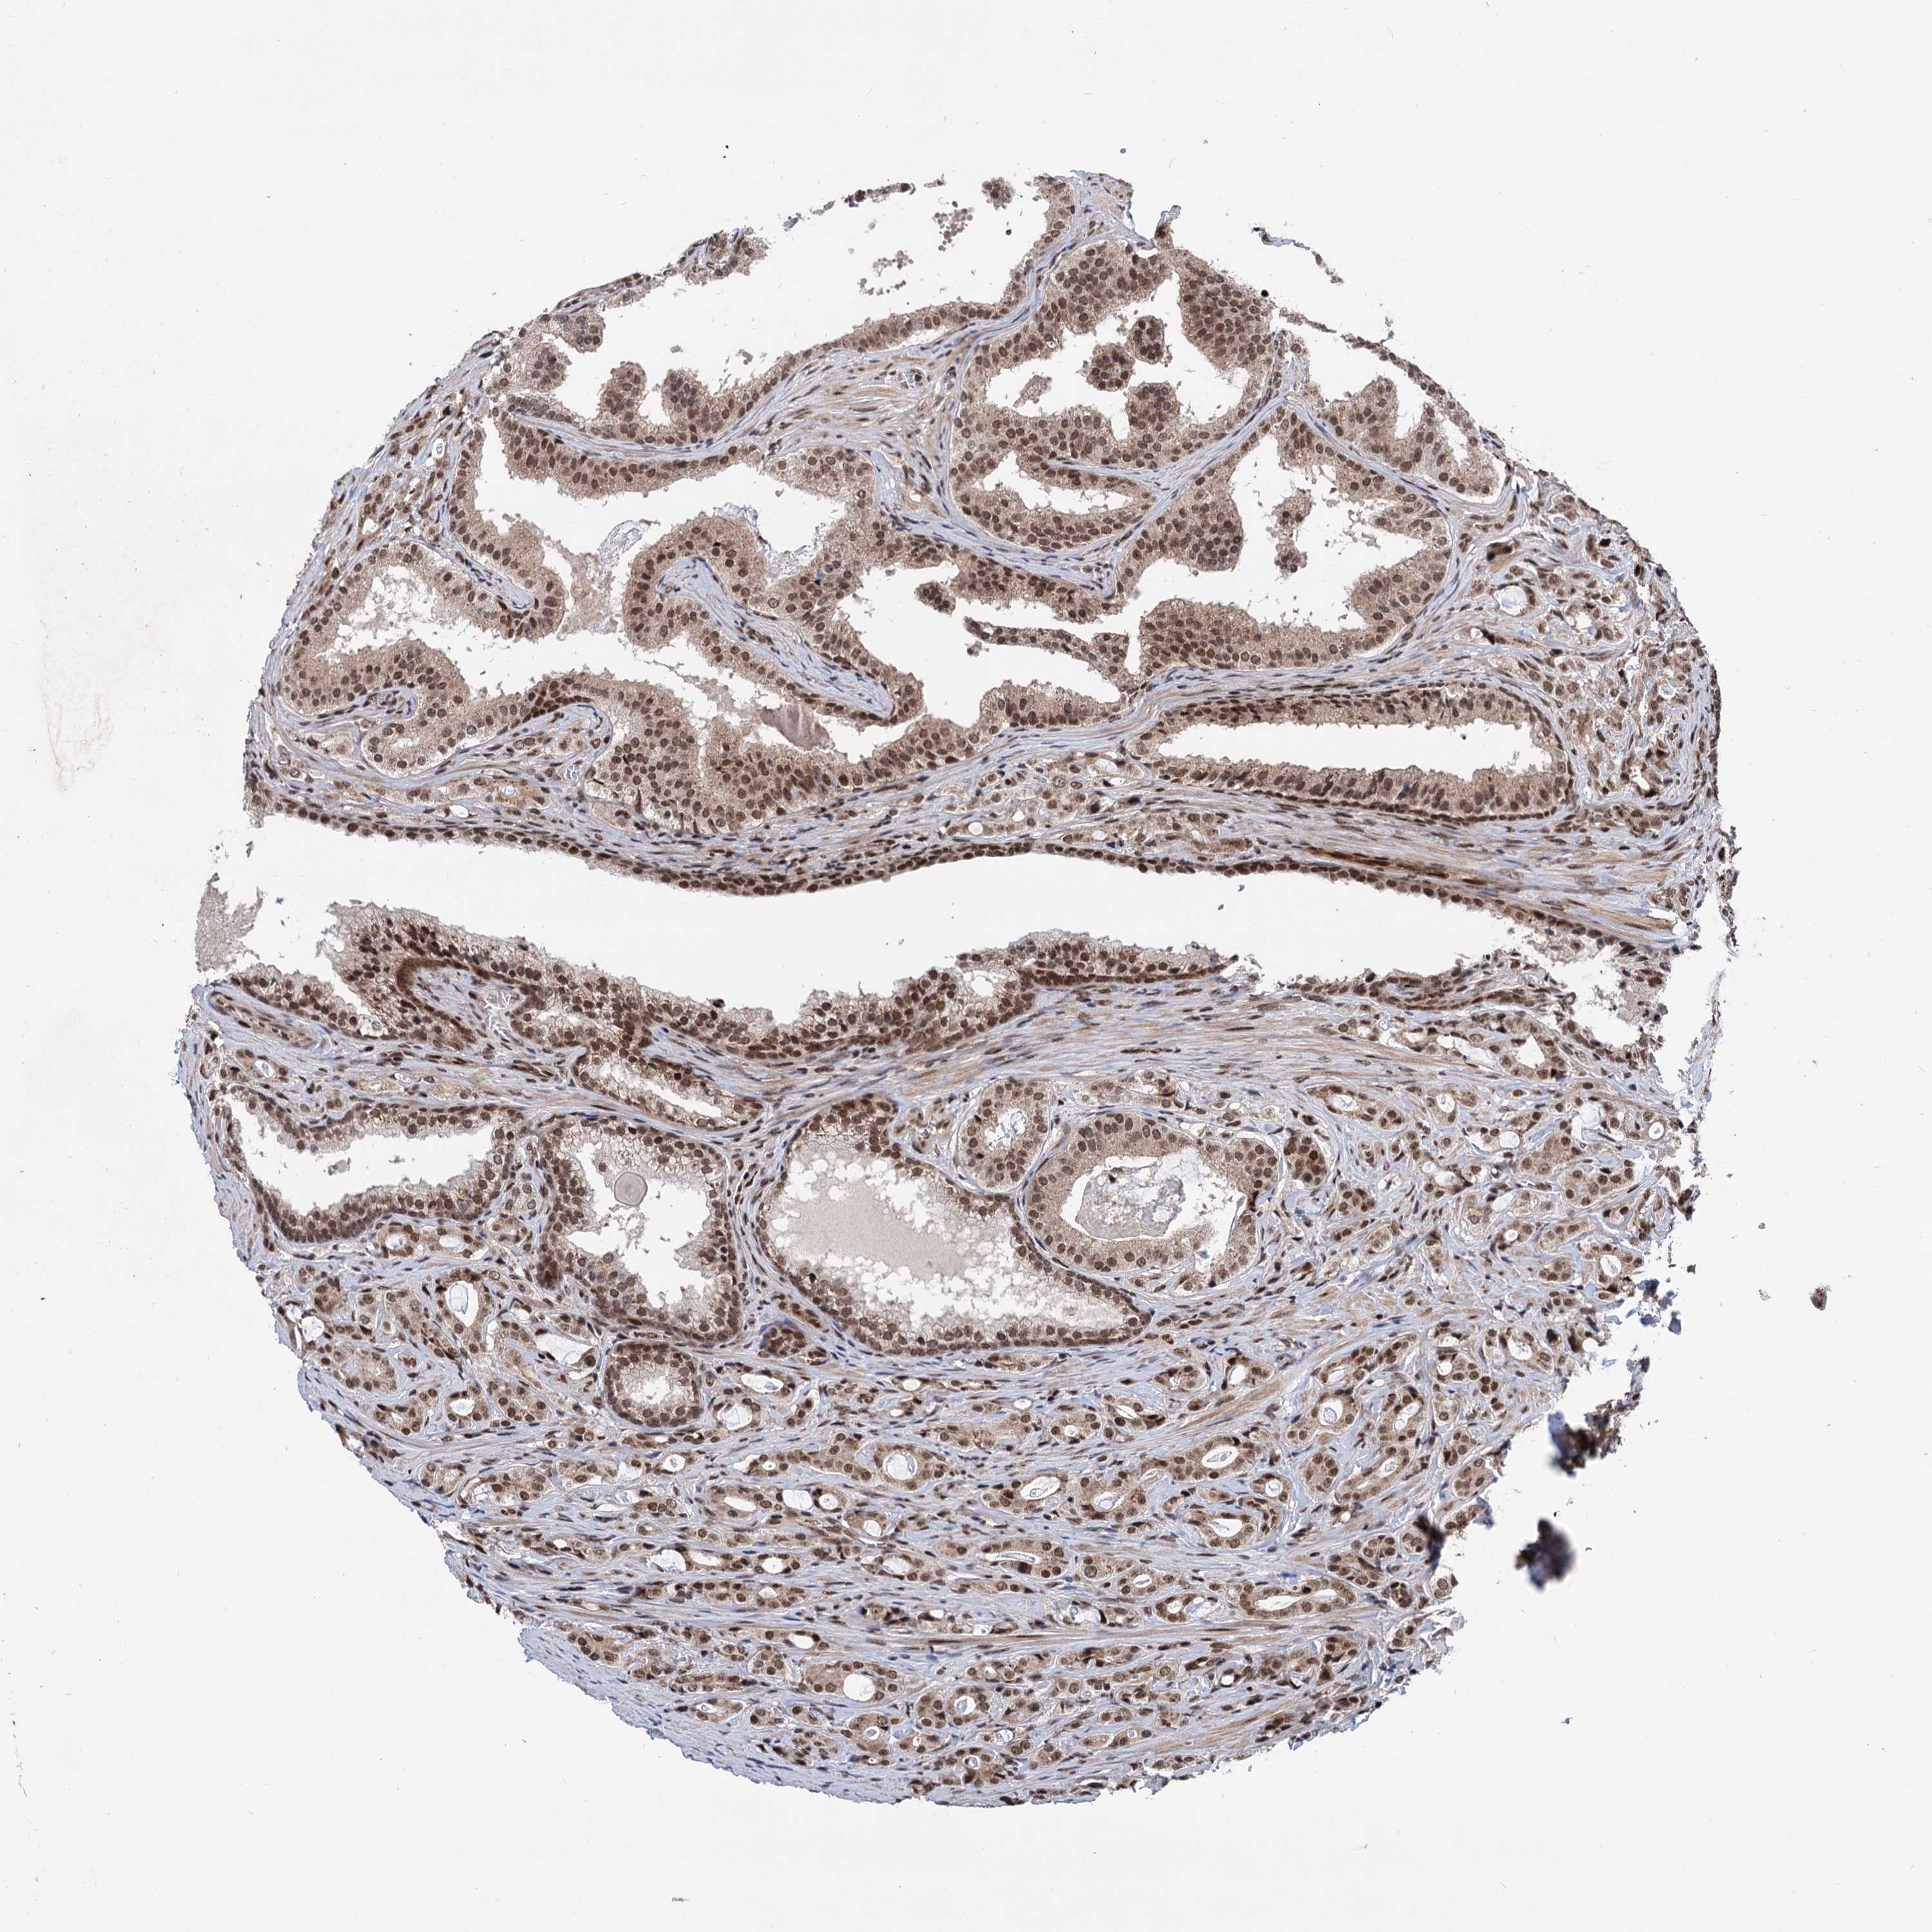

PROSTATE CANCER - Protein expressioni

A mouse-over function shows sample information and annotation data. Click on an image to view it in a full screen mode. Samples can be filtered based on level of antibody staining by selecting one or several of the following categories: high, medium, low and not detected. The assay and annotation is described here.

Note that samples used for immunohistochemistry by the Human Protein Atlas do not correspond to samples in the TCGA dataset.

Antibody stainingi

Antibody staining in the annotated cell types in the current human tissue is reported as not detected, low, medium, or high, based on conventional immunohistochemistry profiling in selected tissues. This score is based on the combination of the staining intensity and fraction of stained cells.

Each image is clickable and will lead to virtual microscopy that enables deeper exploration of all samples and also displays staining intensity scores, fraction scores and subcellular localization as well as patient and tissue information for each sample.

Antibody HPA037687

Staining

High

Medium

Low

Not detected

Intensity

Strong

Moderate

Weak

Negative

Quantity

>75%

75%-25%

<25%

None

Location

Nuclear

Cytoplasmic/membranous

Cytoplasmic/membranous,nuclear

Adenocarcinoma, NOS

Adenocarcinoma, High grade

Adenocarcinoma, Low grade